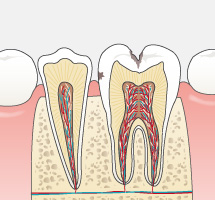

今まで一般的に行われていたむし歯治療は、痛くなったら歯医者に行き治療する、という流れの繰り返しではなかったでしょうか?痛くなってから、むし歯が進行してからの治療は削る・抜歯することが多くなり、徐々に自分自身の天然の歯は「詰め物」や「被せ物」さらには「インプラント」や「入れ歯」になっていきます。天然歯は削ってしまうと二度と元には戻りません。

可能な限りご自身の歯で食事を楽しんだり、話したりして健康な生活を送っていただきたい。だからこそ当院ではできるだけ歯を残す治療をおこないます。単なる対症療法の“削って詰める”ではなく、病原菌の除去をしてからMI(Minimal Intervention:できるかぎり削らず、削っても最小の範囲で)の考えのもと原因療法を施し、治療後はむし歯の再発や新たなむし歯の発生を予防することを目標としています。